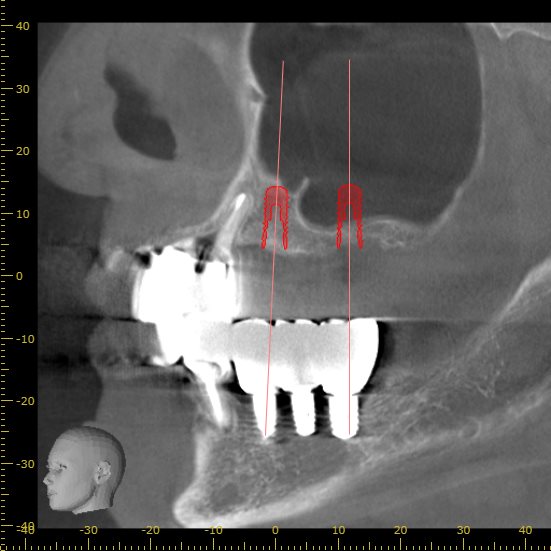

どのサイズのインプラントが適切か判断するため

CT画像を使用し、インプラントのシュミレーションを行います。

後ろのインプラントが副鼻腔に飛び出してしまうのがわかると思います。

現状の骨の状態でインプラントを行うこと自体が難しいと判断できます。

この場合は骨を造成し、インプラントを埋入するための土台を作る必要があります。

今回サイナスリフトと呼ばれる術式をインプラントの手術と併用して行う計画を立てました。